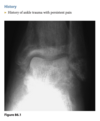

A 65-year-old woman with insulin-dependent diabetes and recent swelling of the left foot

Anteroposterior view of the left foot

(Fig. 2.20.1) demonstrates vascular calcification,

soft-tissue swelling, lateral subluxation of the sec-

ond through the fifth metatarsals in relation to the

cuneiforms, and early destructive changes at the

tarsal-metatarsal joints. Notice the disruption of

the normal parallel alignment of the medial aspect

of the second cuneiform with the medial aspect of

the second metatarsal base (arrow).

Lisfranc fracture-dislocation, homolat-

eral type

On imaging, the Lisfranc

fracture-dislocation is seen as dorsal and lateral dis-

location of the metatarsal bases in relation to the cu-

neiforms. It is the most common dislocation in the

foot.

There are two distinct forms of the Lisfranc

fracture-dislocation: homolateral and divergent. In

the homolateral type, all metatarsals are dislocated

laterally in relation to the cuneiforms.

In the divergent type, there is lateral displacement of

the second through the fifth metatarsals and medial

or dorsal shift of the first metatarsal.

The characteristic radio-

graphic changes include soft-tissue swelling, vascular

calcification, bone destruction and fragmentation,

multiple fractures, and soft-tissue ossific debris from

the destructive changes

MR imaging can be useful in detecting bone marrow

edema, subcutaneous abscess, and sinus tracts